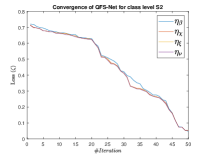

The suitable tailoring of the phase angle in the Hadamard gate advocates the stability of the QFS-Net or its convergence which is very crucial for self-supervised networks where the loss function (here error function) is dependent on the interconnection weights. Hence, the phase angles are evaluated using and as given in Equations 18 and 21, respectively. It is worth noting that the qutrit based quantum neural network provides faster convergence compared to the classical neural networks. This is due to the fact that whereas the classical neural networks are formed using the multiplication of input vector and the weight vector guided by an activation function, the quantum-based networks incorporate the frequency components of the weights and their inputs thereby enabling faster convergence of the network states. This inherent novel feature of the quantum neural networks facilitates the qutrit based fully self-organized quantum algorithm to be employed in QFS-Net to converge super-linearly, as shown in Figure 3. The loss function cum QFS-Net network error function is defined on quantum measurement in the following way.

where, represents the true interconnection weight terms of the inter-connection weights as expressed using the Hadamard gate () at an instance (). is a coherent error function of and . Convergence analysis of the proposed qutrit-inspired QFS-Net is provided in Appendix Section -A and demonstrated experimentally with qubit embedded QIS-Net [39] as shown in Figure 3. It can be summarized that the convergence of the QFS-Net is faster than that of the QIS-Net and also follows super-linearity. This claim is also substantiated by the number of iterations required to converge for each image slice in QFS-Net and QIS-Net as illustrated in Figure 4.